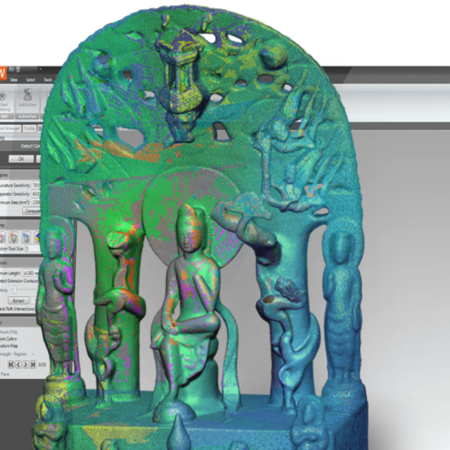

The process for studying natural knees is more difficult since CAD models of the bones are not readily available. To create models of natural knees, Fregly’s team uses CT scans, which produce static 2D image slices from the top to the bottom of a patient’s leg. The CT data are then imported into sliceOmatic image-processing software from TomoVision, where a 3D point cloud model is created by stacking the 2D axial images of patients’ legs.

Beyond Point Cloud Data

When studying natural knees with fluoroscopy, the problem becomes how to turn the point cloud data obtained from sliceOmatic into accurate 3D models of the bone surfaces. Banks requires highly detailed surface models - the more precise the surface representation, the better the fluoroscopic image-matching results.

“We need to go beyond point cloud data and develop accurate representations of the curves and contours inherent in an organic, biological surface,” says Fregly. “Most off-the-shelf engineering tools are not adequate for this purpose.”

This is where 3D photography, the process of capturing a physical object and automatically processing it as an accurate digital model, comes in. Fregly’s team uses Geomagic Wrap software from 3D Systems to create detailed polygonal models from the point cloud data. These models use small triangles to create surface representations that are ideal for shape-related tasks such as image matching.

Fregly uses Geomagic Wrap’s curvature-based hole-filling to extrapolate missing surface data at the ends of the bones caused by the finite slice thickness that is inherent in medical imaging data. Next he uses a curvature-based decimation algorithm to reduce the number of polygons required to accurately represent each biological surface. The final decimated model can then be compared to the original point cloud data using Geomagic Wrap’s tolerance functionality to determine the accuracy of the polygonal surface fit.

Segmented CT scan slices are stacked to form a point cloud model of the femur

Geomagic Wrap is used to create a detailed polygonal model from the point cloud data.

The polygonal surface deviates from the point cloud model by no more than 0.2 millimeters.